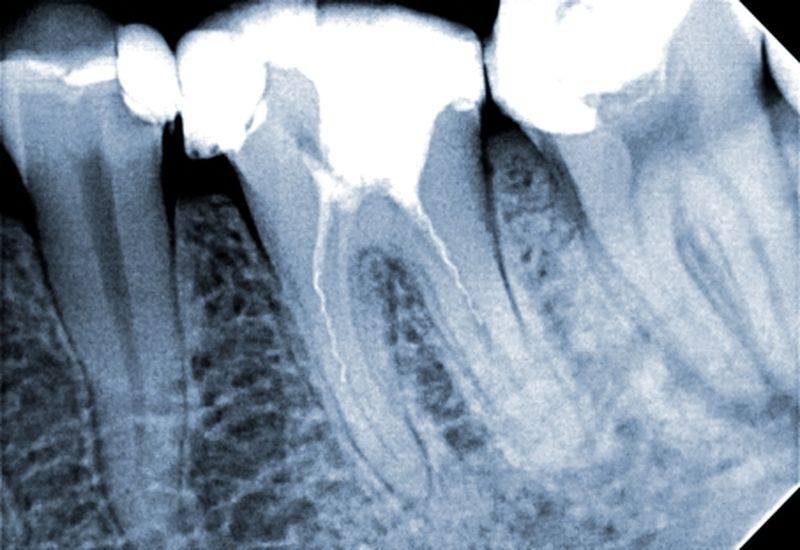

Stan po wypełnieniu ostatecznym kanałów korzeniowych poszczególnych zębów.